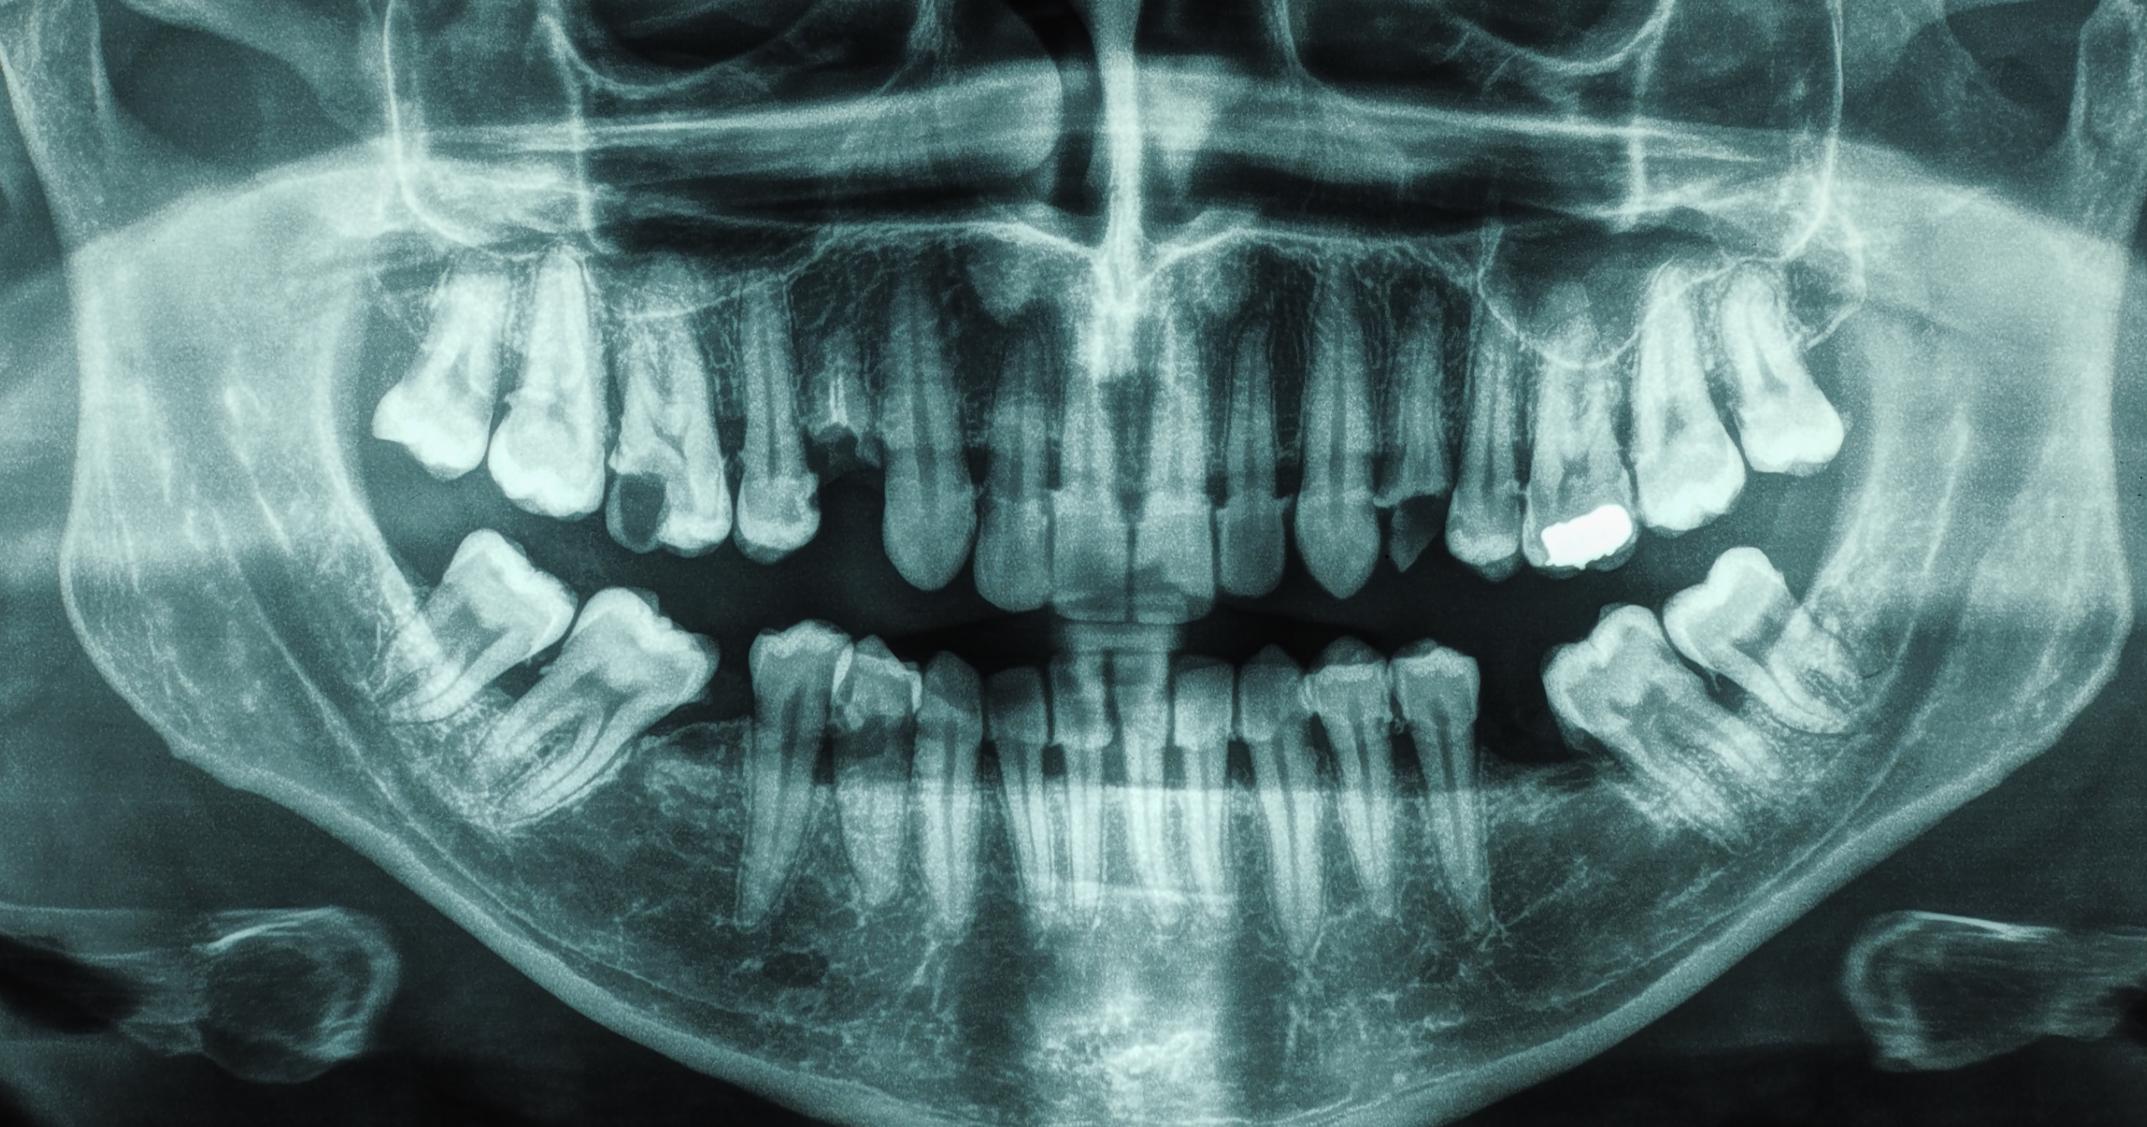

Tooth position can cause teeth grinding. If a person has missing or crooked teeth, they're more likely to grind their teeth in their sleep. Though occasional grinding is not a cause for concern, regular teeth grinding can lead to oral health complications and damage to the teeth. For individuals who grind their teeth because of their tooth position, their dentist will typically fit them with a mouth guardto help protect the teeth during sleep. Individuals may also want to consider braces to correct any severely misaligned teeth. Teeth can move and shift at any age, meaning adults may need braces even if their teeth were straight throughout their youth. Being proactive about orthodontic health can increase overall health, along with helping self-esteem.